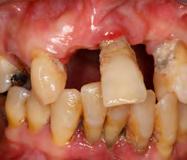

Las Figuras 1-3 muestran las imágenes de la cavidad bucal de la paciente. Se puede observar el deterioro generalizado de la salud bucodental, destacando la higiene dental deficiente, gingivitis, restauraciones dentales desajustadas, exposiciones radiculares, anodoncias parciales y caries radiogénica.

Las Figuras 4-13 son imágenes radiográficas de los dientes de la paciente que presen tan múltiples lesiones periapicales como consecuencia de las necrosis pulpares originadas por la radioterapia. Se realizaron los

tratamientos y retratamientos endodónticos necesarios para preservar los dientes en boca, evitando las exodoncias y por lo tanto minimizando el riesgo de generar osteorradionecrosis.